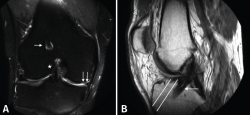

Figura 2. Resonancia magnética de la rodilla derecha. A: imagen coronal en secuencia STIR en la que se aprecian la plastia del ligamento cruzado anterior (LCA; estrella) y el túnel femoral (flecha) verticalizados, con meniscectomía medial amplia (doble flecha); B: imagen sagital en secuencia T1 en la que se aprecia el túnel tibial posterior a la situación anatómica del LCA (flecha). Líneas blancas: representación de la situación ideal del túnel tibial.

En las pruebas complementarias actualizadas presentaba, en las radiografías simples (Rx) anteroposteriores en carga de ambas rodillas (Figura 1A), un túnel femoral muy vertical, con un dispositivo de suspensión como material de fijación y algunos cambios degenerativos incipientes en el compartimento medial. En la Rx lateral de rodilla (Figura 1B) presentaba un túnel tibial muy posterior. En la resonancia magnética (RM) (Figura 2), persistía la integridad de la plastia inicial del LCA, además de los hallazgos descritos en las Rx, así como una meniscectomía amplia.